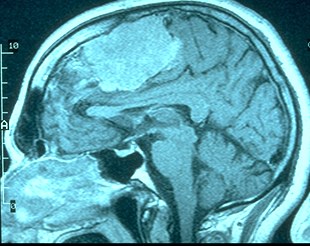

[MRI

Image Tumor]

MRI (Magnetic Resonance Imaging): 3-dimensional images created by subjecting body to radio waves under strong magnetic fields. Computers can recreate image of inside of the body.